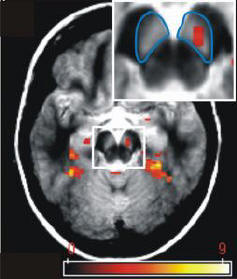

haben nachweisen können, dass die Konfrontation mit neuen Informationen

während des Lernens die Gedächtnisleistung verbessert. Die Forscher

vermuten, dass Neuigkeiten eine bestimmte Region im Mittelhirn - die

Substantia nigra oder Area ventralis tegmentalis - aktiviert. |

Foto: Klinikum der

Otto-von-Guericke-Universität Magdeburg |

Die Vermutungen der Forscher wurden in einer Reihe von praktischen

Experimenten sowie durch Messungen der Gehirnaktivität mithilfe der

funktionellen Magnetresonanztomographie (fMRI) bestätigt. In der ersten

Versuchsreihe wurden den Probanden Bilder von bekannten sowie

unbekannten Außenaufnahmen und Gesichtern dargeboten. Die Substantia

nigra/Area tegmentalis ventralis des Mittelhirns reagierte

ausschließlich auf neue Bilder, obwohl manche der bekannten Bildern

emotional negativ waren und etwa ein wütendes Gesicht oder ein

Autounfall darstellten. Im zweiten Experiment wurden die Testpersonen